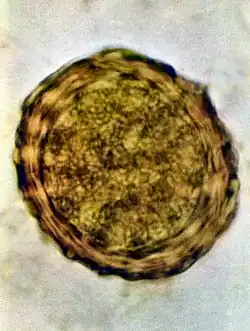

Infertile egg

Ascaris lumbricoides is characterized by its great size. Males are 2–4 mm (0.08–0.2 in) in diameter and 15–31 cm (5.9–12 in) long. The male's posterior end is curved ventrally and has a bluntly pointed tail. Females are 3–6 mm (0.1–0.2 in) wide and 20–49 cm (7.9–19 in) long. The vulva is located in the anterior end and accounts for about one-third of its body length. Uteri may contain up to 27 million eggs at a time, with 200,000 being laid per day. Fertilized eggs are oval to round in shape and are 45–75 μm (0.0018–0.0030 in) long and 35–50 μm (0.0014–0.0020 in) wide with a thick outer shell. Unfertilized eggs measure 88–94 μm (0.0035–0.0037 in) long and 44 μm (0.0017 in) wide.[9]